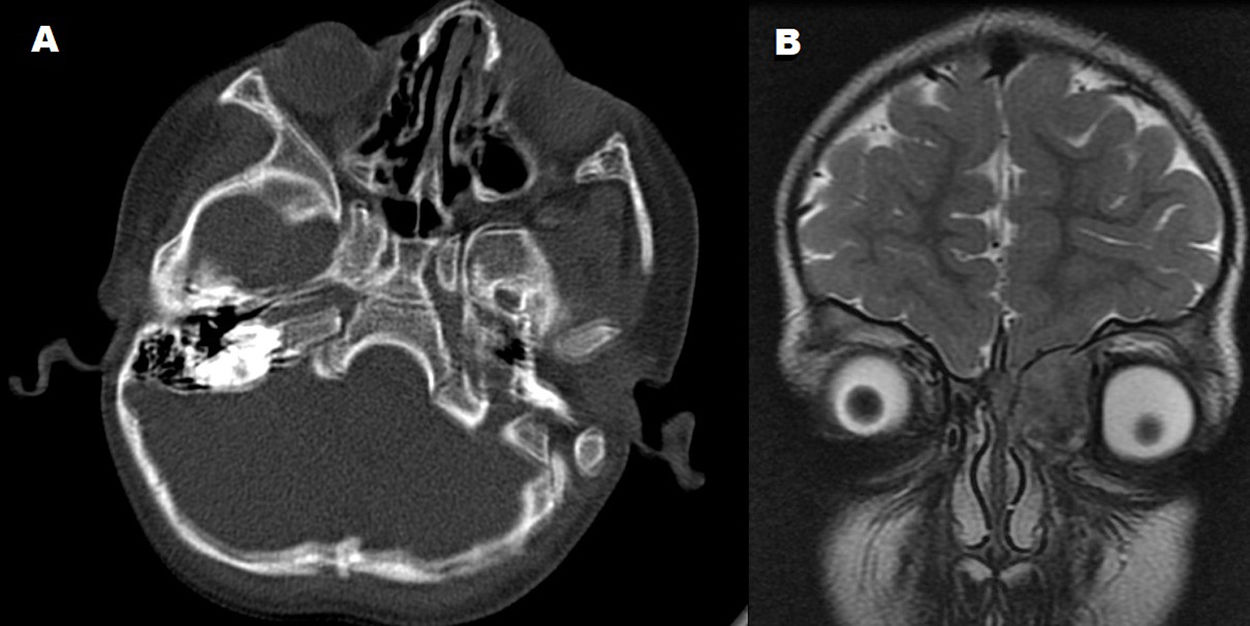

Langerhans cell histiocytosis (LCH) is a myeloid neoplasm characterized by clonal neoplastic proliferation of Langerhans-type dendritic cells associated with an inflammatory infiltrate predominantly composed of lymphocytes and eosinophils. In this article, we present an unusual case of LCH with significant swelling in the left lacrimal sac region in a 3-year-old child, clinically mimicking acute dacryocystitis. Microscopically, it showed intense inflammatory infiltrate and histiocytes with irregular nuclei. The tumor cells were positive for S-100 protein, CD1a, and CD207 (langerin). Molecular study was positive for the V600E/E2/D mutation (EXON 15). This case emphasizes the importance of careful clinical, radiographic, and microscopic evaluation, as some neoplasms may mimic common benign lesions.